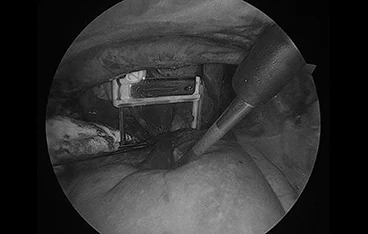

C-arm 투시 영상장비를 이용해 심장 내부에 기생하는 사상충을 정밀하게 제거합니다

6. 유미흉 및 기관 질환 진단·치료

가슴 속에 액체가 차는 유미흉, 기관허탈 등 호흡기 문제를 내시경 장비로 진단하고 최소침습적으로 치료합니다.